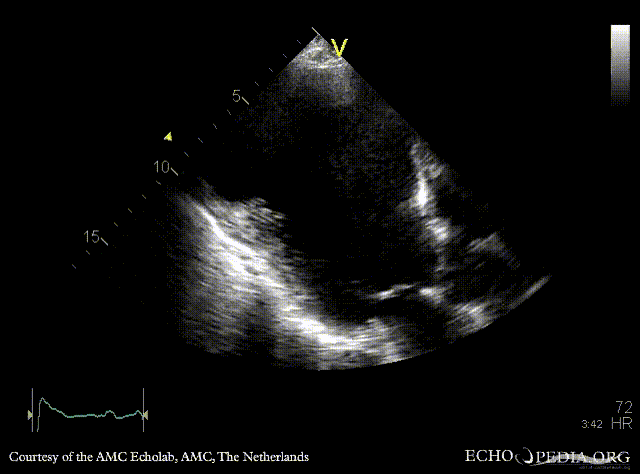

PSAX: dilated left ventricle, poor function